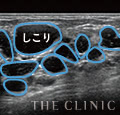

失敗例2

30歳・3年前に注入

左胸のみ、しこりができてしまったようです。最新エコーで診察したところ、最大5cmもの大きなしこりであるため、豊胸施術時に吸収されないほどの大きな塊で注入されたことが原因でしょう。ヒアルロン酸は吸収・消失される程度のサイズで注入することが重要です。